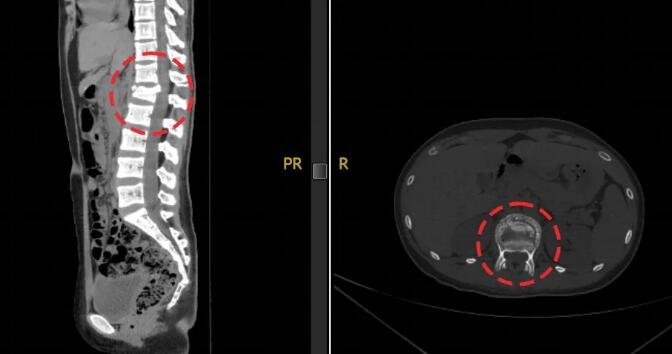

△小蕊腰椎伤处透视影像

经检查,小蕊腰椎前、中、后三柱均有骨折,双侧足踝粉碎性骨折,尤其是左踝距骨碎成了很多块。这个爱打篮球的姑娘,面临后半生行走困难的危险。

△腰椎伤处术后影像